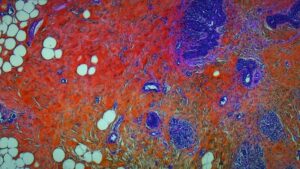

H・P・ラヴクラフト作品すら彷彿させる漁船のカオスを映し出した『リヴァイアサン』を手掛けたあのコンビだけに、今回も本編には一切のナレーションやテロップなし。GoProを最先端医療カメラに持ち替え、頭部にはじまり眼球、消化器官から子宮・胎盤、そして胸椎までをパックリゴリゴリに映し出す。言葉を選ばずに言えば、めちゃくちゃグロテスクな映像の連続である。